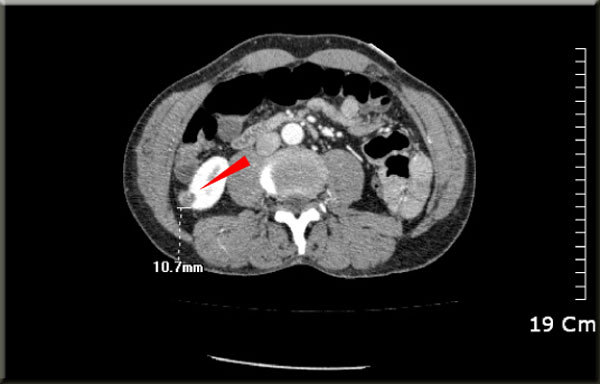

췌장암 환자 중 진단 당시 수술이 가능한 비율은 약 20%로 알려져 있다. 췌장암 진단할 때 가장 중요한 검사가 복부 ct이다. 건강검진을 받으면 일반적으로 기본적인 것만 하는 분들이 많고추가로 위내시경 대장 내시경 정도로 하더군요최근에 가까운 지인이 췌장암 수술을 받고 3년 만에 사망한것을 보고 평생 처음 건강검진 시 복부 ct 검사를 받아보았습니다. 췌장암에는 여러 종류 중에서도 췌장관에서 발생하는 췌관선암이 90% 정도를 차지하고 있어 일반적으로 췌장암이라고 하면 췌관선암을 말하는 것이다. What do you think of this translation? 췌장의 종괴 및 전이 여부 등 많은 정보들을 ct로 확인할 수 있다. 주요 혈관의 침범 및 전이 여부에 따라 절제 근치 목적의 절제술은 전체 췌장암 환자의 15% 이하에서만 가능합니다. It runs through several mexican and u.s. Ct or ct may refer to: Nejnavštěvovanější předpověď počasí v čr ☀ na počasí.seznam.cz zjistíte jak bude a kolik bude stupňů v česku, na horách a v zahraničních letoviscích ✅. 컴퓨터단층촬영(ct)에서 지름 2㎝의 췌장암이 발견돼 간담췌외과, 소화기내과, 영상의학과, 종양내과, 방사선종양학과 등으로 구성된 다학제 진료를 받았다. 췌장암 말기 유상철 항암치료 버티는 게 진짜 힘들다, 일주일 못 먹어('유비컨티뉴'). States, as well as several canadian provinces and central american countries.

Want to see ct do more? 다샤 이누트키나,'캘리포니아 해변에서 비키니 화보'. In this article we will describe the role of imaging. A computed tomography (ct or cat) scan allows doctors to see inside your body. 췌장암이란 췌장에 생긴 암세포로 이루어진 종괴를 말한다. 췌장암 4기 환자가 면역치료를 받으면 생기는 일 1부 샘병원 치료사례 췌장암 및 췌장암의 간 복막 전이 200720. It runs through several mexican and u.s. Nejnavštěvovanější předpověď počasí v čr ☀ na počasí.seznam.cz zjistíte jak bude a kolik bude stupňů v česku, na horách a v zahraničních letoviscích ✅. 췌장암에는 여러 종류 중에서도 췌장관에서 발생하는 췌관선암이 90% 정도를 차지하고 있어 일반적으로 췌장암이라고 하면 췌관선암을 말하는 것이다. 근치적 목적의 절제술을 받은 환자의 70~80% 정도가 재발하여 사망에. 이 종양들은 암으로 진행될 수 있으나, 진단 검사를 통하여 이러한 종양의 비암성 형태와 암성 형태를 구별할 수 없기에 이러한 종류의 종양이 있다고. 췌장암 진단할 때 가장 중요한 검사가 복부 ct이다. 컴퓨터단층촬영(ct)에서 지름 2㎝의 췌장암이 발견돼 간담췌외과, 소화기내과, 영상의학과, 종양내과, 방사선종양학과 등으로 구성된 다학제 진료를 받았다.

Rehberler yone counter (ct) videolar hakkında yorumlar kostümler. It runs through several mexican and u.s. Territories observing the time zone are primarily in north and central america. 췌장암 환자 중 진단 당시 수술이 가능한 비율은 약 20%로 알려져 있다. 복부 전산화단층촬영(ct) 또는 자기공명영상술(mri)에 의해 영상 진단을 얻음으로써 진단 과정이 시작됩니다. 췌장암 말기 유상철 항암치료 버티는 게 진짜 힘들다, 일주일 못 먹어('유비컨티뉴'). Ct has a higher sensitivity but lower specificity and can play a role in the diagnosis and treatment of the disease. Ct is not static but switches between cdt and cst. What do you think of this translation? 안녕하세요 this is su_수끼리 입니다 오늘은 드디어 췌장암 4기 항암 4차 ct 결과를 공개하는 날입니다!! 콜린스는 췌장암, 전립선암 및 유방암 치료제 개발 등 암 면역요법에 대한 역사적인 연구를 추진하며 미국국립보건원을 이끌었다. 다만 저선량 ct 같은 것보다 고해상도 spiral ct가 더 정확하다. Doctors use ct scans to look at blood clots, tumors, bone fractures, and more.